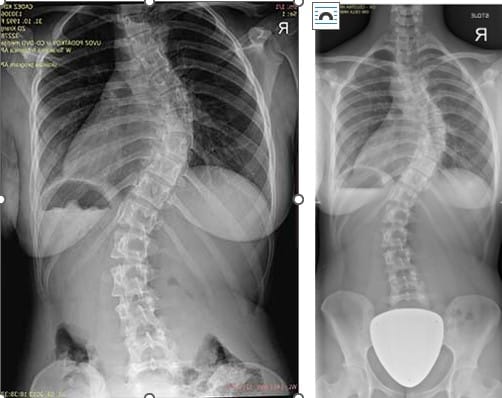

Skolioza predstavlja okvaro hrbtenice v čelni ravnini. Kaj to pomeni? Če bi gledali človeško telo od spredaj, bi morala biti njegova hrbtenica ravna, v primeru skolioze pa je ukrivljena, kot primer na spodnji sliki.

Po enem letu dela, sem naredila rentgen, da bi dejansko videla, kaj se dogaja s hrbtenico. Pa sem bila razočarana.

Res je, da je sliki težko primerjati, saj je leva slika slikana od blizu, ne zajema celotnega ramenskega obroča, niti vratu, niti celotne medenice.

Stanje je malenkost boljše, obe krivini sta se zmanjšali za par °,ampak moj cilj ni, da ostane približno enaka, temveč da jo konkretno izboljšam.

Mogoče bi bilo smiselno poudariti, da pri opravljanju rentgena ne stojiš sproščeno, temveč te osebje »naštima« v položaj, ki izgleda normalen. Pri desni sliki (slikano 2019), sem imela občutek, da sem zelo nagnjena v desno, po tem, ko me je osebje postavilo v »normalen« položaj.